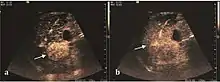

These lesions have various patterns (hypo or hyperechoic) with at least 1 cm diameter. They are hepatocytes with dysplastic changes, but without clear histological criteria for malignancy. They are divided into low-grade dysplastic nodules, where cellular atypia are mild and high-grade dysplastic nodules with moderate or severe cellular atypia, but without any established signs of malignancy. Occasionally, well-differentiated HCC foci can be identified in high-grade dysplastic nodules (appearance called "nodule in nodule") . Most authors accept the carcinogenesis process as a progressive transformation of DN from low-grade to high-grade and into HCC. The nodule's vasculature changes progressively, correlated with the degree of malignancy, and it is characterized by decrease until absence of portal venous input and by increase of arterial intratumoral input. Neoformation vessels occur with increasing degree of dysplasia. Arterial neovascularization is enhanced in a chaotic and explosive way, while normal, arterial and portal vasculature continues to decline. High-grade dysplastic nodules are hypovascularized both arterial and portal phases, while early HCC nodules may have similar arterial pattern with the surrounding parenchyma or exacerbated, and portal hypovascularization. In moderate or poorly differentiated HCC (classic HCC) tumor nutrition is performed only by neoformation vessels (abundant), the normal arterial and portal vasculature completely disappearing. This behavior of intratumoral vascularization is typical for HCC and is the key to imaging diagnosis.

B-mode ultrasonography is unable to distinguish between regenerative nodules and borderline lesions such as dysplastic nodules and even early HCC. Doppler examination also has a low sensitivity in differentiating dysplastic nodules from early HCC. Doppler signal may be absent in both regenerative and dysplastic nodules. Some authors indicate the presence of venous type Doppler flow which reflects the portal venous nutrition of the nodule as a characteristic feature of dysplastic nodules and early HCC (Minami & Kudo, 2010). Other authors noticed the presence of an arterial flow with small frequency variations and a normal resistivity index. On CEUS examination both RN and DN may have quite a variable enhancement pattern. Generally, both nodules enhances identically with the surrounding liver parenchyma after UCAs injection. Dysplastic nodules are hypovascular in the arterial phase. In case of highgrade dysplastic nodule sometimes a hypervascularization can be detected, but without associating "wash out" during portal and late CEUS phases. In these cases, biopsy may clarify the diagnosis.

The suggestive appearance of early HCC on 2D ultrasound examination is that of hypoechoic nodule, with distinct pattern, developed on cirrhotic liver. Hypoechoic appearance is characteristic of moderate/poorly differentiated HCC, with low or absent fatty changes. Rarely, HCC may appear isoechoic, consist of a tumor type with a higher degree of differentiation and therefore with slower development. Another common aspect is "bright loop" or "nodule-in-nodule" appearance, hypoechoic nodules in a hyperechoic tumor.

Spectral Doppler characteristics of early HCC overlap those of the dysplastic nodule, as they are represented by the presence of portal venous signal type or arterial type with normal RI (well differentiated HCC) or increased RI (moderately or poorly differentiated HCC). The CFM exploration identifies a chaotic vessels pattern.

On CEUS examination, early HCC has an iso- or hypervascular appearance during the arterial phase followed by wash out during portal venous and late phase. There are studies showing that the wash out process is directly correlated with the size and features of neoplastic circulatory bed. Thus, highly differentiated HCC illustrates the phenomenon of late or even very late "wash out" while poorly differentiated HCC has an accelerated wash out at the end of arterial phase. It is therefore mandatory to analyze all these three phases of CEUS examination for a proper characterization of liver nodules. Tumor wash out at the end of the arterial phase allows the HCC diagnosis with a predictability of 89.5%. Some authors consider that early pronounced contrast enhancement of a nodule within 1–2 cm developed on a cirrhotic liver is sufficient for HCC diagnosis. These results prove that for a correct characterization of the lesions it is necessary to extend the examination time to 5 minutes or even longer.